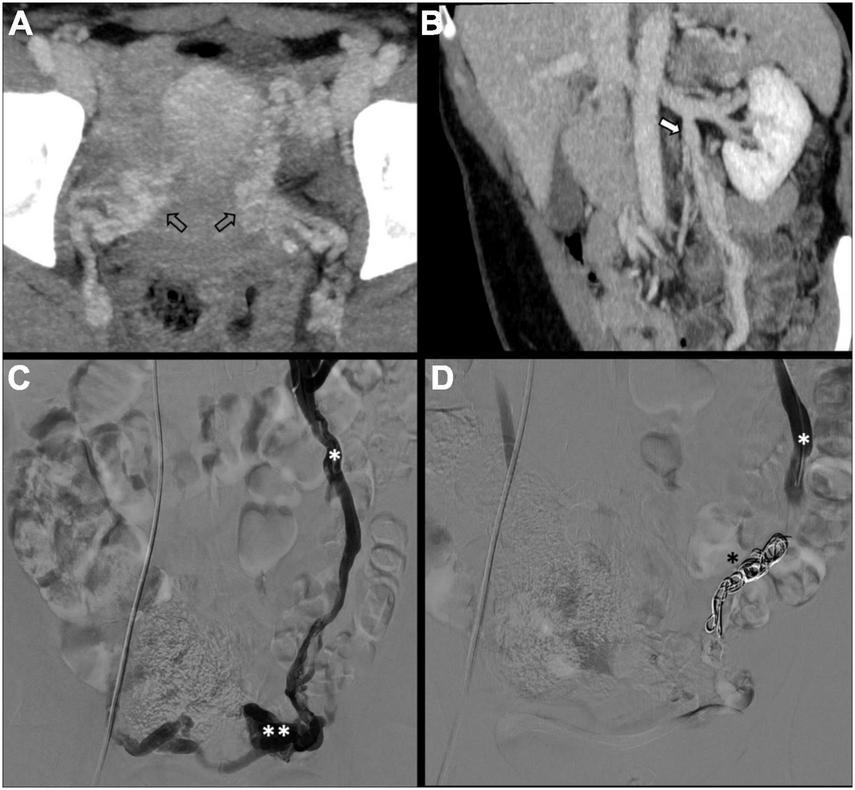

There is no consensus on how to report results, and the final results are very heterogeneous. Though, few studies, systematic reviews, and randomized trials have displayed no remarkable differences between embolization materials in terms of outcome (16, 79, 86). Furthermore, studies have reported an overall rate of complete, excellent, or moderate improvement of 75% at 4–8 weeks and more than 80% at an average of 45 months post-procedure, regardless of the technique or agent used (16, 87–90). Figure 2 shows an example of type Ia pelvic varices and subsequent vaso-occlusive therapy by means of multiple endovenous coils. Endovascular vaso-occlusive therapy is also applicable in the nutcracker phenomenon, with reported improvement in 56 to 98% of patients (17). Figure 3 shows an example of nutcracker phenomenon corresponding to a IIb pelvic varix stage. In the case of arteriovenous fistula (type IV pelvic varices), distal embolic efficacy can be achieved with liquid agents, as shown in Figure 4.

FIGURE 2

Type Ia pelvic varices in a 48 yo female due to unilateral venous insufficiency. (A,B) Computed tomography (CT) phlebography shows pelvic varices (open arrows) with a dilated left ovarian vein (white arrow). (C,D) Conventional phlebography and CT phlebography show pelvic varices (double white asterisks) with a dilated left ovarian vein (single white asterisk), treated with multiple coils (single black asterisk).